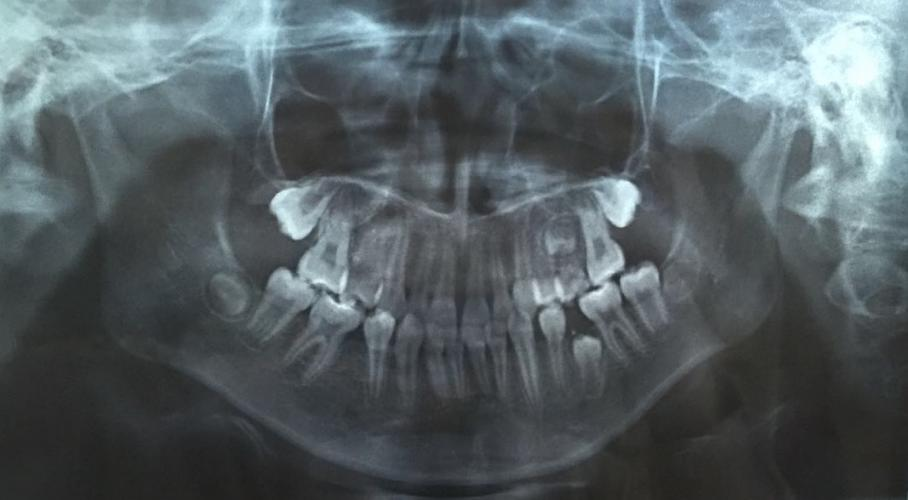

兒童口腔科副主任醫(yī)師王銳副教授為琦琦拍攝了一張曲面斷層片,發(fā)現琦琦左下后牙區(qū)有一顆牙齒因間隙不足阻生,建議家長接受矯正調節(jié),擴開間隙,觀察阻生于頜骨內的牙齒是否可以順利萌出。調節(jié)過程相對復雜,調節(jié)周期較長,需要每隔一個月復診一次。“孩子今年上初中,課業(yè)壓力越來越大,但既然牙齒出現這么嚴重的問題,擠時間也要積極配合醫(yī)生調節(jié)。”面對這種情況,琦琦媽媽無奈的說。

據王銳副教授介紹,孩子的乳牙脫落要及時到醫(yī)院拍攝曲面斷層片觀察是否存在乳牙早失、恒牙阻生或發(fā)育異常等情況,一旦發(fā)現乳牙早失必須及時制作間隙保持器保留牙齒間隙,給恒牙足夠的萌出空間,避免嚴重后果。